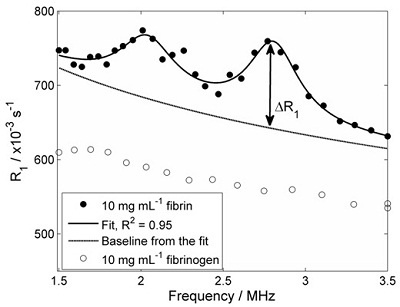

Blood clot formation (thrombosis) involves the controlled polymerisation and cross-linking of fibrinogen to form a network of fibrin fibres which form the rigid skeleton of the clot. Fibrinogen protein is dissolved in blood plasma; due to its mobility in solution, it does not give rise to quadrupolar peaks in its R1 dispersion plot. However, the polymerisation of fibrinogen and its cross-linking to form a fibrin network leads to immobilisation of the protein, and the associated observation of quadrupole peaks.

In this study model thrombi were produced in the laboratory, using a range of starting concentrations of fibrinogen in solution. Clot formation was initiated by the addition of thrombin enzyme, after which FFC relaxometry was carried out on the 1-mL (approximately) samples, using our bench-top FFC-NMR relaxometer. The figure below shows an R1 dispersion plot of fibrinogen solution at 10 mg/mL concentration (open circles), together with a dispersion plot obtained after clot formation (closed circles).

R1 dispersion plots of fibrinogen in solution (open circles) and fibrin clot (closed circles). Quadrupole peaks are absent prior to clotting, but evident afterwards due to immobilisation of the protein The experiment was repeated using a range of starting concentrations of fibrinogen, in order to see if the 'height' of the quadrupole peaks (ΔR1 in the figure above) was proportional to the immobile protein concentration. The figure below shows the result of these experiments:

Effect of fibrinogen concentration on the 'height' of the quadrupole peaks ΔR1. The expected linear relationship is observed. This study showed that FFC-NMR relaxometry can monitor clot formation in a model of thrombosis. Work is progressing to investigate more complex thrombosis models. We plan to extend this work, in the hope that FFC-MRI can provide extra information on blood clots in patients.